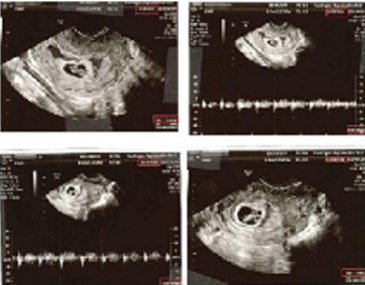

第三代试管婴儿自1990年诞生以来,从最初的只能筛查5-7对染色体发展成至今不仅可以对胚胎所有染色体(共23对)进行筛查 ,还可以深入到单基因进行了解。第三代试管婴儿归根结底是不仅仅选择外表看似正常的胚胎,更要在体外对胚胎进行染色体检查,选择染色体正常的胚胎植入子宫,理论上可以提高“试管婴儿”的成功率,这就是胚胎植入前遗传学筛查。 1. 发展历史: 最初的第三代试管婴儿一般采用荧光原位杂交技术(FISH)的方法,能够同时检测不超过8对染色体,但是人类染色体有23对,其中5~7对染色体正常,仍然有可能存在其他染色体的异常,而没有被发现,所以才有了之后技术的发展。但泰国目前的第三代试管婴儿仍然只检测3对染色体。 2. 第三代试管婴儿作用: 35岁卵子畸变率已经超过45%,之后逐年升高。其实,身为女性自身也能有所感受:不采取避孕措施,夫妇双方各项生理检查均正常,为什么试孕1年都怀不上,问题可能就出在卵子上。如果盲目移植不健康的胚胎会有怎样不好的结局?一、移植后不着床;二、孕期流产;三、具有出生缺陷或者遗传疾病。但是由于可以筛选性别所以国内目前严格限制技术应用。而第三代试管婴儿由于在移植前即进行检查,则可淘汰不健康的胚胎,在很大程度上规避了流产的风险,同时可以明确知道胎儿性别。 | ![]() |